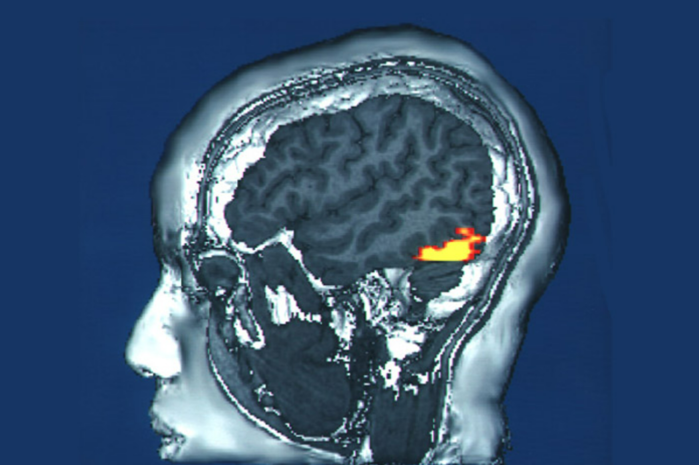

| ▲ 1980년대에 연구자들은 측두엽의 이 영역이 얼굴 인식에 관여한다는 사실을 발견했다. © 미국 국립보건원 |

"얼굴이 기형이 된 겁니다!“이 사건은 당시 이미 우리에게 얼굴을 구별하는 특정 뇌 영역이 있다는 의혹을 불러일으켰다. 1990년대 초만 해도 측두엽이 그럴 가능성이 높은 곳으로 여겨졌다. 그러나 스탠퍼드 대학교의 요제프 파르비지(Josef Parvizi)가 이끄는 연구진은 이 안면 중추가 정확히 어디에 위치하고 2012년에 어떻게 반응하는지, 그것도 우연의 일치로 밝혀냈다. 뇌전증 치료를 준비하기 위해, 연구진은 환자의 뇌에 전극을 삽입하고 측두엽의 여러 영역을 자극했다.

갑자기 그 남자가 소리쳤다. "방금 다른 사람으로 변했어요. 얼굴 모양이 바뀌었잖아요!" 자세히 살펴보니 측두엽의 한 주름, 소위 방추상회(fusiform gyrus)에 있는 두 개의 작은 세포 덩어리가 이러한 현상의 원인인 것으로 밝혀졌다. 이 두 신경 세포핵을 자극하면 환자의 얼굴 인식이 변화한다. 파르비지는 "저도 환자만큼 놀랐다"고 회상했다.